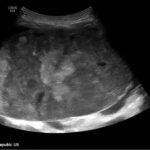

A 5-month-old female presented to the emergency department with worsening abdominal distention and postprandial emesis. Point-of-care ultrasound (POCUS) demonstrated extensive abdominal free fluid with a large, heterogeneous mass in the suprapubic region. This was confirmed on computed tomography (CT) of the abdomen and pelvis. The patient was urgently taken to the operating room for exploratory laparotomy where a ruptured tumor was discovered. The patient was eventually diagnosed with ovarian juvenile granulosa cell tumor. POCUS can be vital in guiding the recognition of rare pediatric conditions in the emergency department and should be considered in patients where there is concern for an acute abdomen.